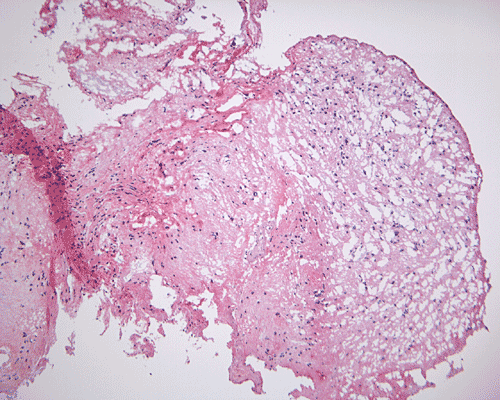

There is no endothelial proliferation or necrosis. An  intraoperative diagnosis of glial neoplasm was made. The lesion was entirely resected. On paraffin section, the lesion has a hypocellular background decorated by many small microcysts, often in clusters, that contain mucoid material and small cluster of nuclei that resemble bundles of flowers (Panel I and J).  The nuclei are bland. There was no mitosis, endothelial proliferation or necrosis (Panel K and L).